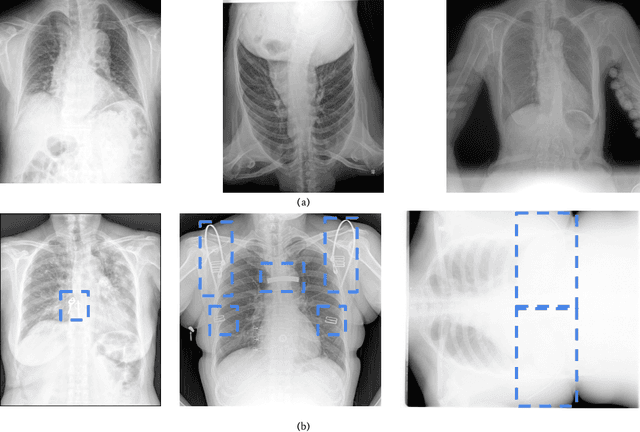

Abstract:Medical image quality assessment is an important aspect of image acquisition, as poor-quality images may lead to misdiagnosis. Manual labelling of image quality is a tedious task for population studies and can lead to misleading results. While much research has been done on automated analysis of image quality to address this issue, relatively little work has been done to explain the methodologies. In this work, we propose an explainable image quality assessment system and validate our idea on two different objectives which are foreign object detection on Chest X-Rays (Object-CXR) and Left Ventricular Outflow Tract (LVOT) detection on Cardiac Magnetic Resonance (CMR) volumes. We apply a variety of techniques to measure the faithfulness of the saliency detectors, and our explainable pipeline relies on NormGrad, an algorithm which can efficiently localise image quality issues with saliency maps of the classifier. We compare NormGrad with a range of saliency detection methods and illustrate its superior performance as a result of applying these methodologies for measuring the faithfulness of the saliency detectors. We see that NormGrad has significant gains over other saliency detectors by reaching a repeated Pointing Game score of 0.853 for Object-CXR and 0.611 for LVOT datasets.

Abstract:To maintain a standard in a medical imaging study, images should have necessary image quality for potential diagnostic use. Although CNN-based approaches are used to assess the image quality, their performance can still be improved in terms of accuracy. In this work, we approach this problem by using Swin Transformer, which improves the poor-quality image classification performance that causes the degradation in medical image quality. We test our approach on Foreign Object Classification problem on Chest X-Rays (Object-CXR) and Left Ventricular Outflow Tract Classification problem on Cardiac MRI with a four-chamber view (LVOT). While we obtain a classification accuracy of 87.1% and 95.48% on the Object-CXR and LVOT datasets, our experimental results suggest that the use of Swin Transformer improves the Object-CXR classification performance while obtaining a comparable performance for the LVOT dataset. To the best of our knowledge, our study is the first vision transformer application for medical image quality assessment.